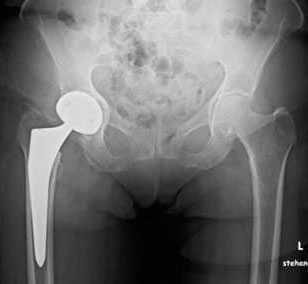

Пациент К. 68 лет, на протяжении 1 года отмечал постепенное нарастание болей и ограничение амплитуды движений в правом тазобедренном суставе. Обратился в К+31 в августе 2017 года, при выполнении рентгенографии выявлен асептический некроз головки правого бедра, коксартроз 3 стадии.

Выполнено тотальное эндопротезирование правого тазобедренного сустава эндопротезом фирмы Zimmer бесцементной фиксации, пара трения керамика\полиэтилен. Гладкое течение послеоперационного периода.

Рентгеногграммы после операции, положение компонентов эндопротеза правильное. Пациент активизирован на следующий день после операции, обучен ходьбе с дополнительной опорой на ходунки. Вторые сутки после операции, пациент ходит по палате и коридору без посторонней помощи с дополнительной опорой на ходунки.

Пациент выписан на 4 сутки после операции в удовлетворительном состоянии. В настоящее время функция опоры и ходьбы полностью восстановлена, ходит без дополнительной опоры, боли не беспокоят, восстановился нормальный стереотип походки.